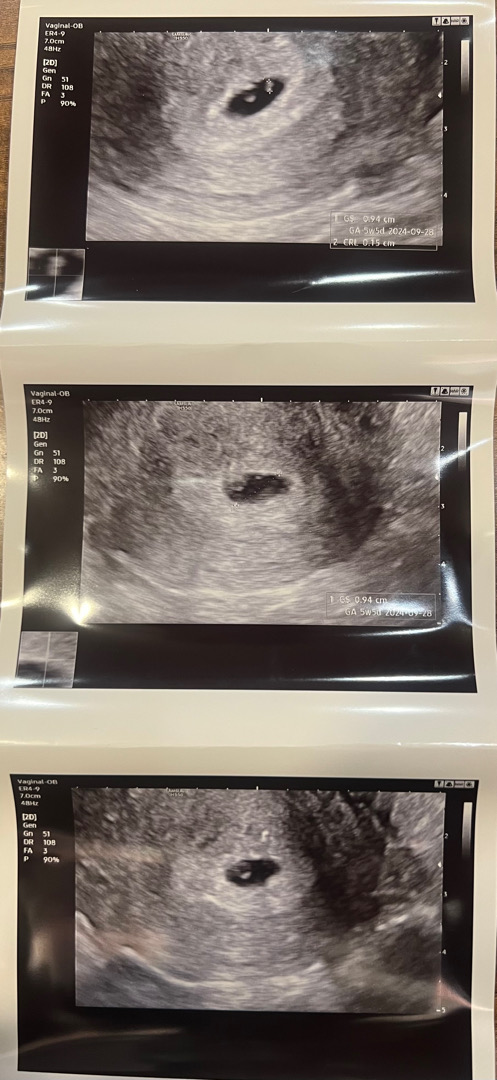

6주 3일차인데 심장소리는 아직도 못들었어요😔

자리는 잘 잡은거 같은데 저게 아가인지 아직 단정할수 없다고, 일주일 후에 다시 병원 방문하라고 하네요... 기대했는데 실망이 더 큰거 같아요😞 우울하네요 정말😷